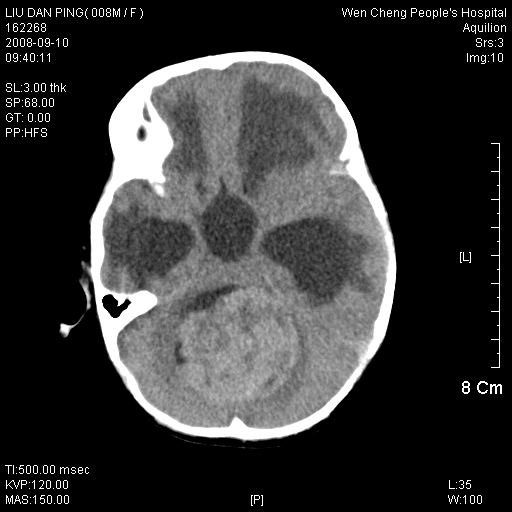

以下是引用卜一在2008-9-10 16:21:00的发言:[br]髓母细胞瘤伴梗阻性脑积水!支持![br]髓母细胞瘤特点:—般直径大于3.5cm,位于后颅凹中线之小脑蚓部。累及上蚓部的肿瘤延伸到小脑幕切迹之上,ct平扫肿瘤多呈均匀一致的高或等密度病灶,增强检查呈均匀一致的强化。病灶中有小坏死时,平扫亦可呈不均匀之混杂密度,注药后有增强。[br]

以下是引用zjzjr在2008-9-10 15:09:00的发言:[br]髓母细胞瘤伴梗阻性脑积水.